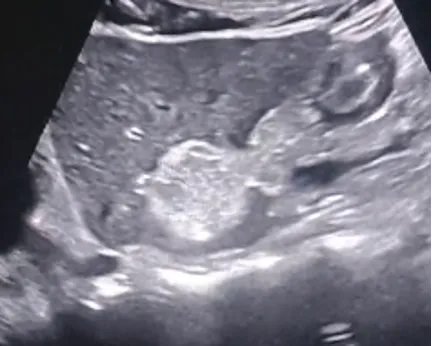

肝细胞癌

定义

是肝内最常见的原发性恶性肿瘤,其恶性程度高、预后差,中老年男性多见。

病理分型

● 巨块型:为单个圆形巨大肿瘤,或由数个癌结节融合而成。癌肿直径大于5cm,少数达10cm以上。

● 结节型:癌结节可单发或多个,直径约1.0~5.0cm不等。可为多中心或肝内转移所致,可伴有肝硬化。

● 弥漫型:较罕见,癌结节大小如绿豆至黄豆不等,其数目众多,弥漫分布于全肝,病程进展迅速,预后极差。

超声表现

● 巨块型肝癌:体积较大,>5cm

高回声多见,多伴有液化坏死

无纤维包膜(浸润性生长)

易并发肝破裂出血

● 结节型:肿瘤直径多在3~5cm,单发或多发

不均匀高回声或低回声为主,与周围肝组织分界较清,外周常有低回声的声晕

常合并肝硬化或慢性肝病史

● 弥漫型:弥漫散布于整个肝脏,直径在1.0cm左右,肝脏形态失常。

以不均匀低回声多见浸润生长,边界不清,外周一般无声晕或包膜回声。

常伴有肝硬化,与再生结节较难鉴别。

● CDFI:大多数为富血供肿瘤。

肿瘤区域内有丰富的彩色血流信号。

高速、高阻。